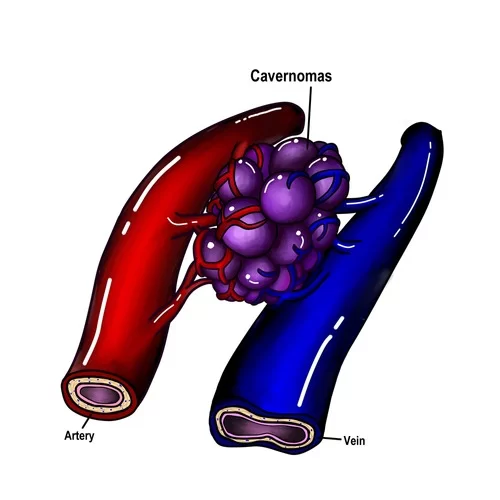

Τα σηραγγώδη αγγειώματα (ή αλλιώς καβερνώματα ή κρυπτικά αγγειώματα ή αιμαγγειώματα-αν και ο τελευταίος όρος είναι λάθος) είναι αγγειακές δυσπλασίες και συγκεκριμένα ένα συνοθύλευμα παθολογικών αγγείων στον εγκέφαλο και μερικές φορές και στο νωτιαίο μυελό (Εικόνα 1). Μοιάζει λίγο με «βατόμουρο» και είναι γεμάτο με αίμα το οποίο ρέει αργά στα αγγεία του. Το μέγεθος μπορεί να ποικίλει, από ελάχιστα χιλιοστά μέχρι μερικά εκατοστά.